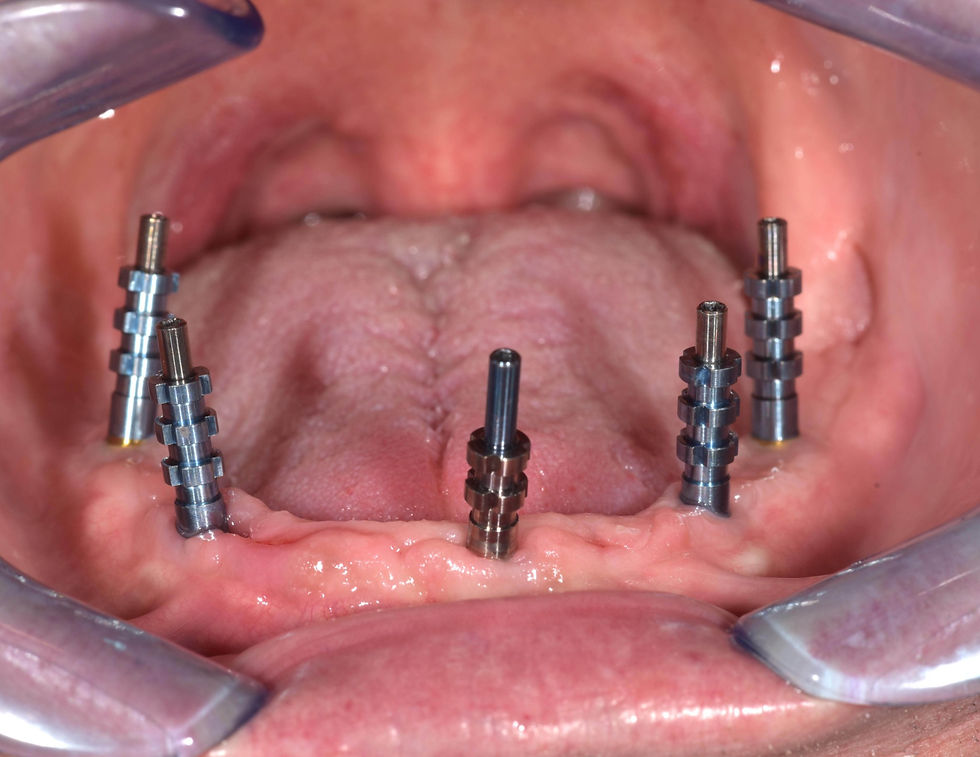

Open tray impression with Pick-up transfer.